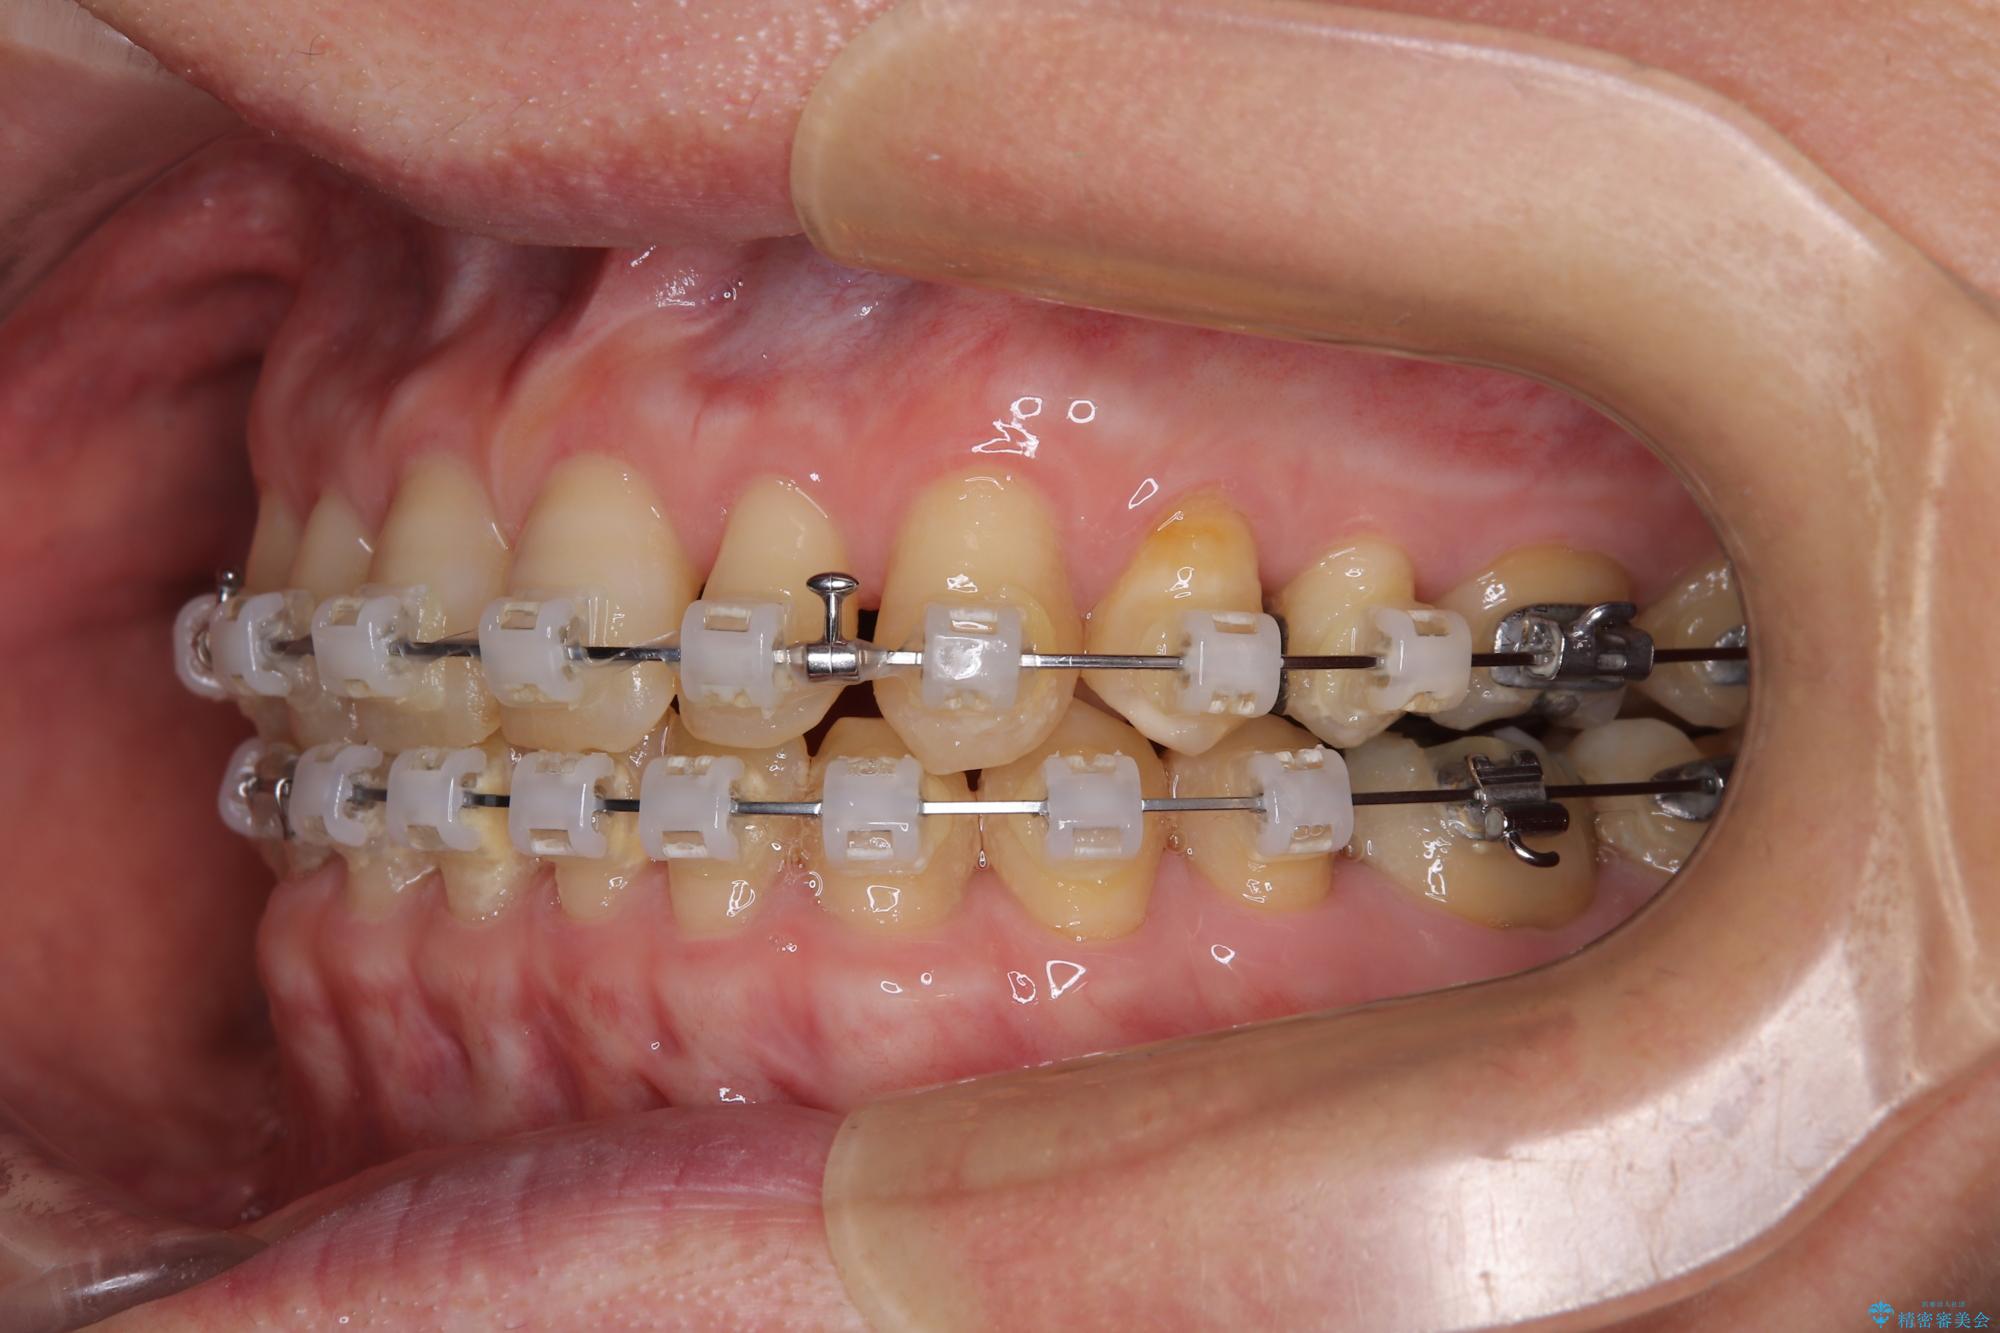

【モニター】ディープバイトで隙間の空いた歯列 ワイヤー装置での非抜歯矯正

- 矯正装置

- クリアブラケット

下顎前歯が隠れるほどのディープバイトにより、強い咬合力と突き上げで上顎歯列に隙間が空いている状態でした。

手前に傾斜している奥歯をワイヤー装置で立ち上がらせ、咬み合わせの高さを挙上することで突き上げを解消し、空隙歯列を改善していくこととしました。

ディープバイトが改善され、睡眠時の食いしばりも緩和され、顎への負担が軽減されました。